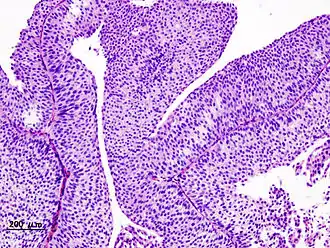

Anatomopathologie

Il existe différents types anatomopathologiques de tumeur maligne de la vessie. Le terme cancer de la vessie correspond au carcinome de la vessie. Il en existe trois formes :

- le carcinome transitionnel (ou carcinome urothélial) est la forme la plus fréquente. Il représente 90 % des cancers de la vessie.

- le carcinome épidermoïde est plus rare, il correspond à 7 % des cancers.

- l'adénocarcinome est plus rare, environ 1 %.

Les tumeurs malignes (cancer) non carcinomateuses correspondent aux lymphomes, sarcomes et tumeurs neuroendocrines de la vessie dont le traitement diffère des carcinomes.